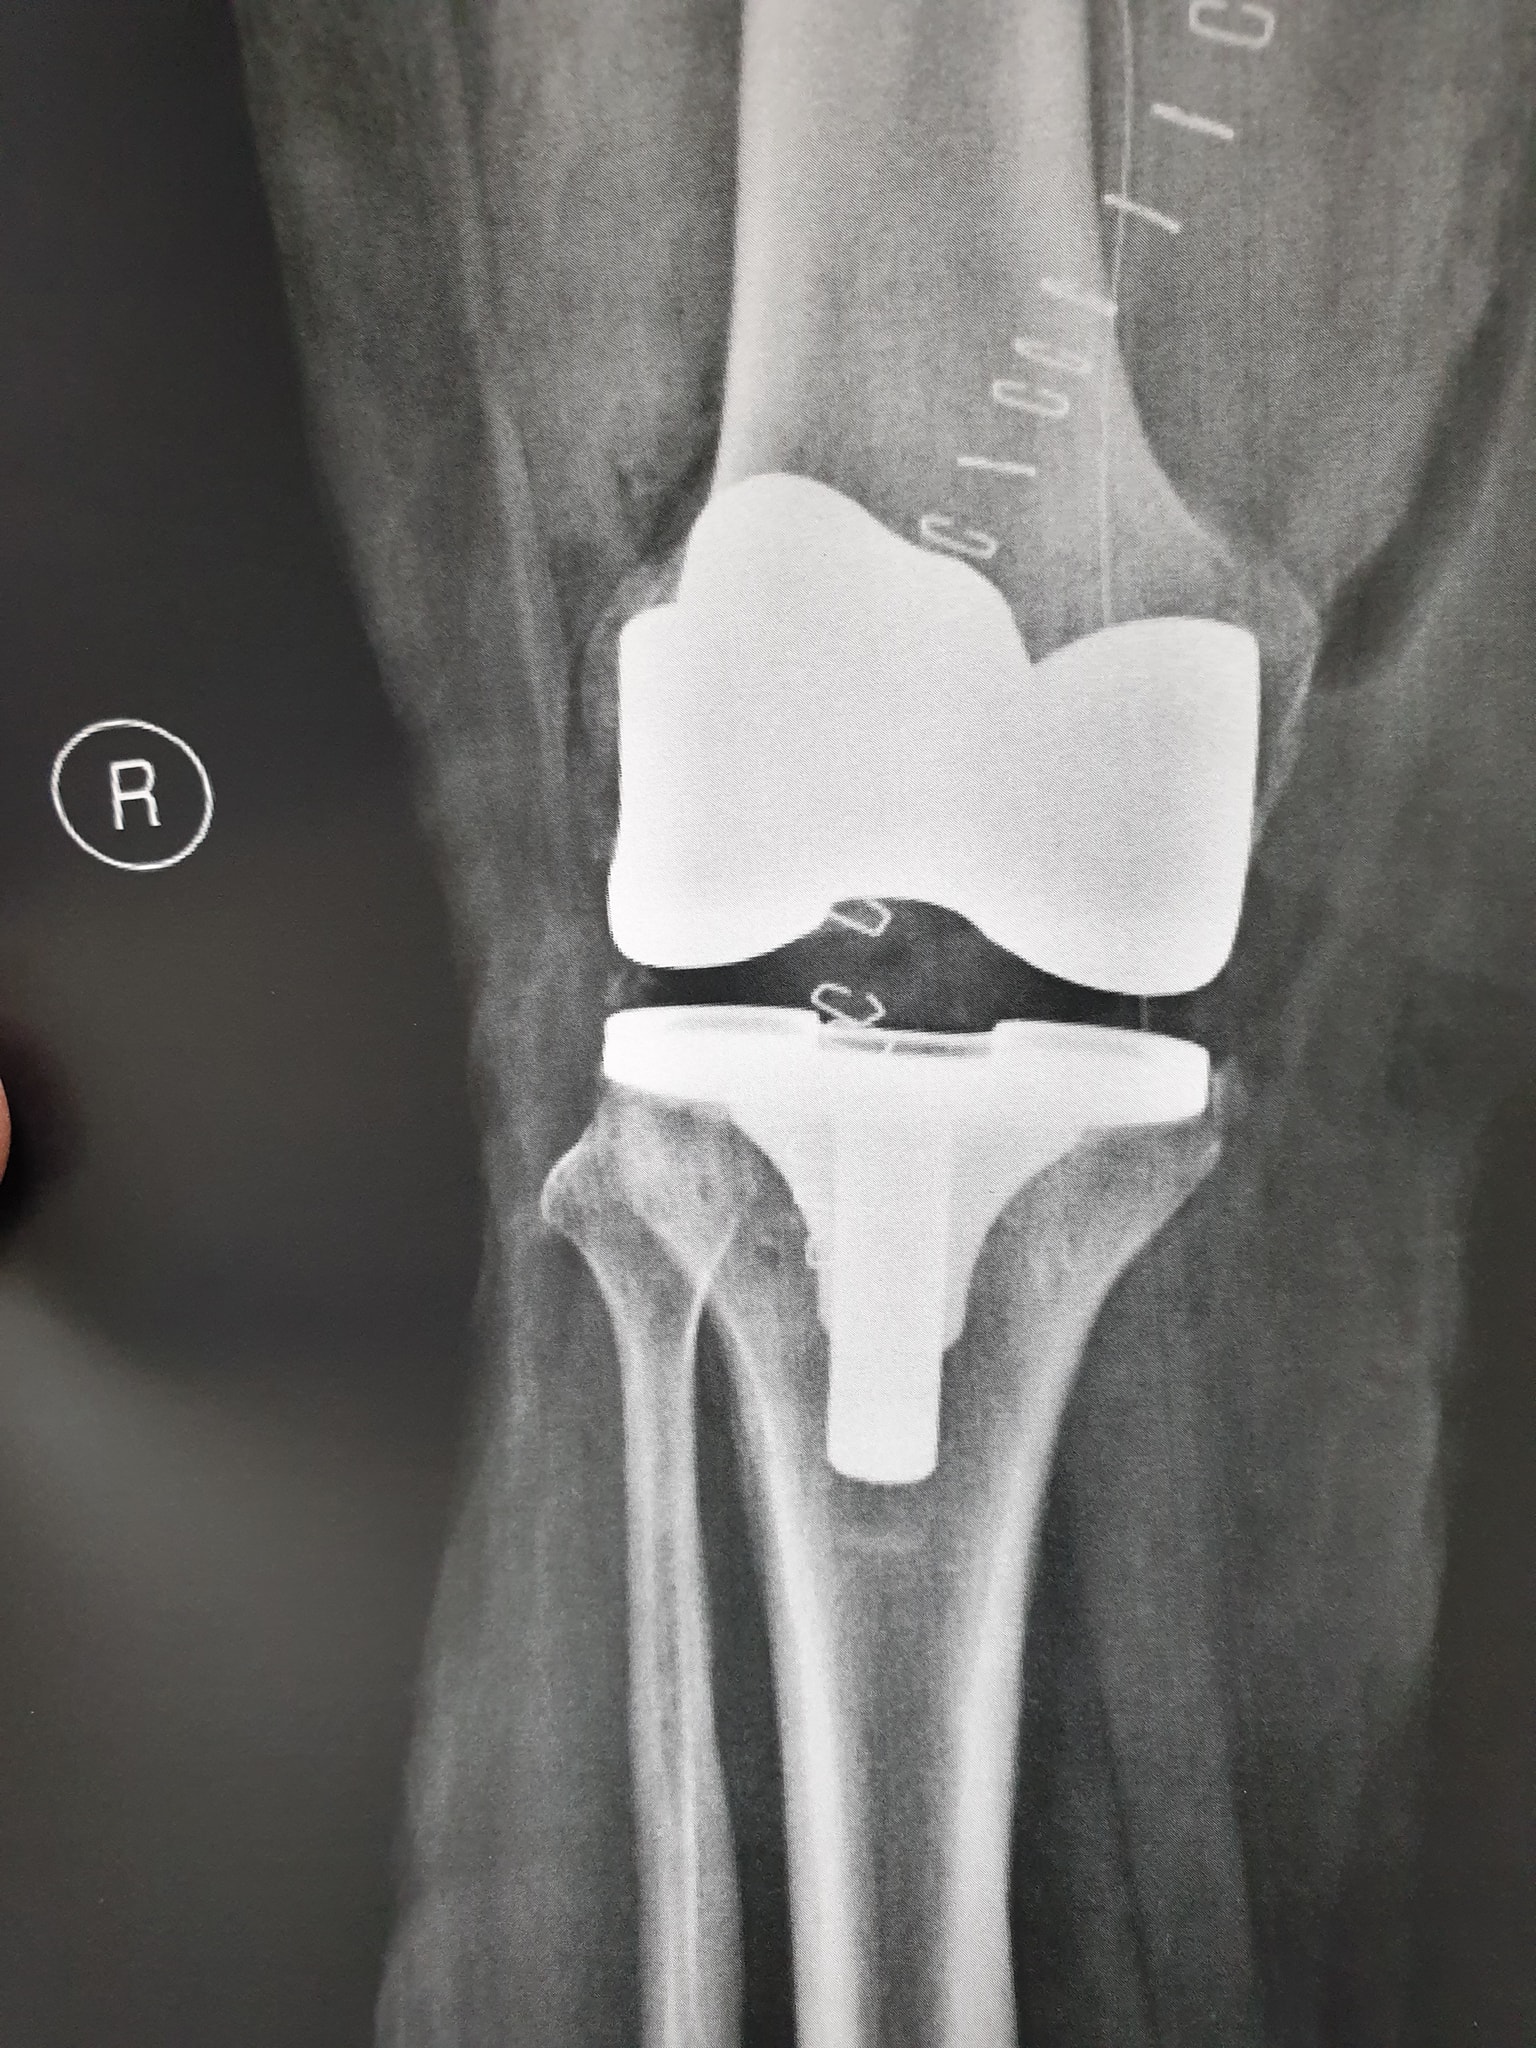

زراعة المفاصل الصناعية ورك و

جراحة العظام والمفاصل